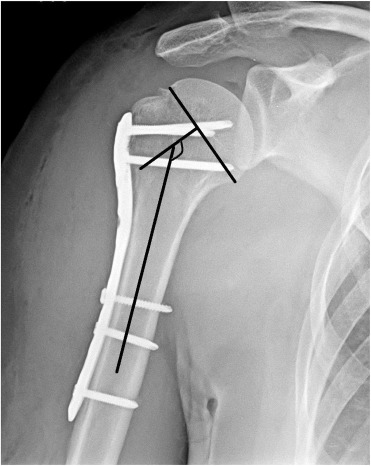

Fig. 3

Fig. 3.

Measurement of head-shaft angle.

Sling immobilization was postoperatively used for 1 week, and passive- and active-assisted range of motion exercises were immediately begun. Active exercises were begun after 4 weeks. Radiographic evaluations were routinely performed at 6 weeks, 3 months, 6 months and 1 year, by using 20° external rotation projection for anteroposterior view and full internal rotation projection for lateral view (Fig. 2 ). If suspicion of fracture healing was present at 3 months, radiographic controls were performed more closely. Fracture healing, complications, and head-shaft angle (HSA) were evaluated radiographically. HSA was calculated by the same surgeon (U.G.), according to the method of Hertel et al.17 (Fig. 3 ). An angle above 130° was considered the goal of treatment. Clinical outcomes were assessed at 1 year of follow-up with Constant score. Nerve lesions were assessed clinically.